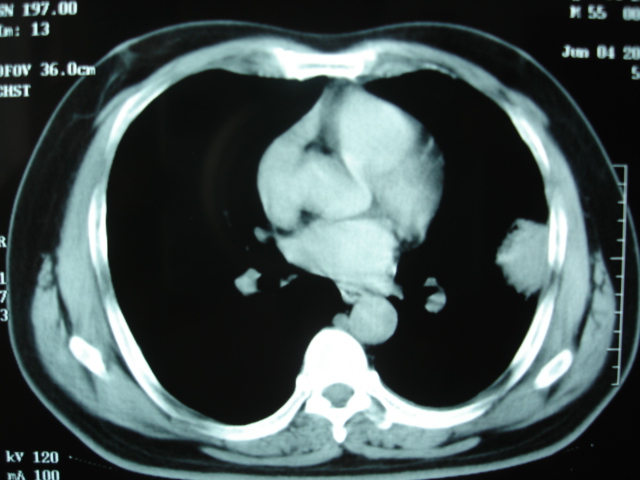

第二次ct2009.6.7 住院后ect未见异常,查痰(阴性)大量抗菌素抗炎一个月后病灶明显变小,7月5号出院后回家后口服抗菌素45天